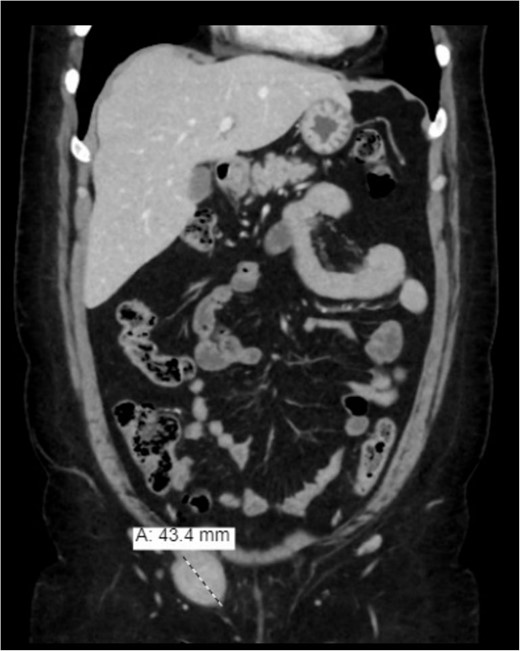

Further assessment by enhanced computed tomography (CT) of the abdomen and pelvis showed a heterogeneously enhanced, well-defined lesion in the right inguinal canal with no surrounding fat stranding or lymphadenopathy. The result corresponded to a hypoechoic lesion seen on the ultrasound with a lamellated appearance, suggesting a nerve sheath tumor or other tumors related to the round ligament, such as leiomyoma/fibroma (Fig. 2). The magnetic resonance imaging (MRI) showed an enhancement and solid lesion in the right inguinal area (Fig. 3).

Enhanced (CT) of the abdomen and pelvis was done, and it showed a heterogeneously enhancing well-defined lesion in the right inguinal canal.